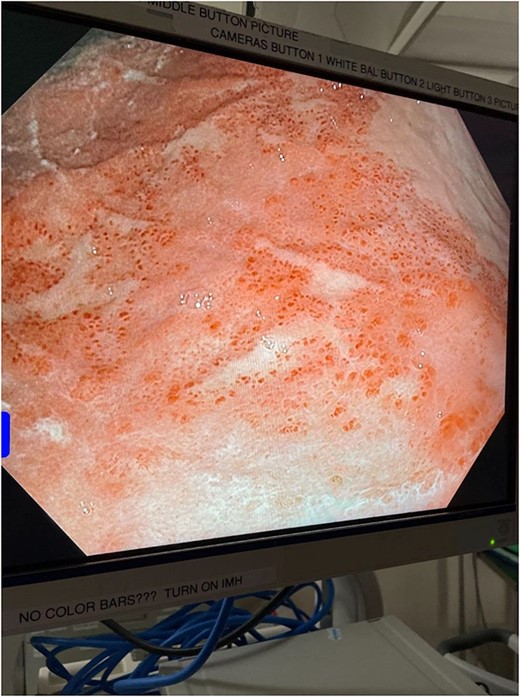

The decision was made to take the patient to the operating room. He underwent diagnostic laparoscopy, which showed a normal gastric antrum; however, on further inspection, a hemorrhagic and inflamed area of stomach was seen proximally at the fundus on the underside of the diaphragm. Next, esophagogastroduodenoscopy was performed, which demonstrated a large black necrotic area in the fundus (Fig. 3), as well as inflammation throughout the rest of the gastric body (Figs 4 and 5). At this point, malignancy could not be ruled out, so the operation was converted to open with a subxiphoid to supraumbilical midline incision. Once in the abdomen and able to further inspect the stomach, the frankly necrotic portion of fundus was noted to be adhered to the underside of the diaphragm and a contained purulent fluid collection was encountered in this area and drained. A partial gastrectomy was then undertaken in similar fashion to a sleeve gastrectomy. The lesser sac was entered and the stomach mobilized along the greater curvature with an energy device up through the short gastrics. A stapler was used to resect the entire necrotic portion of stomach from the midbody to the angle of His. Frozen sections were sent which were negative for malignancy. The remaining stomach was inspected for signs of malignancy, but none were found. For these reasons, no further resection was done. The entire staple line was imbricated due to concern for an ischemic etiology for the patient’s disease process, and two drains were left—one anterior and one posterior to the staple line. Final pathology showed prominent gangrenous necrosis, ulcer and acute necro-inflammatory exudate. Most of the specimen had no viable gastric mucosa, and no malignancy was found.